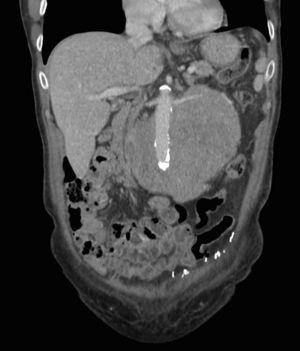

A computed tomography scan showed a heterogeneous retroperitoneal mass measuring 14×11cm surrounding the abdominal aorta and the renal vessels, without invading them (Figs. 1 and 2).

Fig. 1